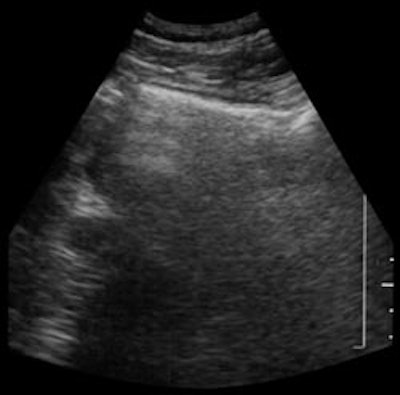

| Shadowing from bowel gas prevents visualization of pancreatic carcinoma (left). Following administration of SonoRx, a large hypoechoic mass is seen in the head of the pancreas (right). Images courtesy of Bracco Diagnostics. | |

Twenty-five patients with suspected pancreatic pathology underwent ultrasonography before and after ingesting 400 ml of SonoRx, a simethicone-coated cellulose oral contrast agent manufactured by Bracco Diagnostics of Princeton, NJ. The agent works by absorbing and dispersing gas bubbles in the stomach, thus reducing shadow artifacts.

"(SonoRx) creates a more uniform interluminal echogenicity, and allows for delineation of the normal gastric wall, and in many cases even the discrete layers," Lev-Toaff said.